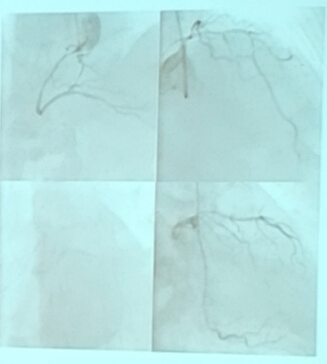

(3)入院两个多月前,因急性下壁、后壁心肌梗死行右冠状动脉支架一枚。仍有活动后胸痛,前降支病变90%狭窄严重伴钙化,拟行前降支旋磨术及支架植入治疗(见图1)。

(4)经桡动脉使用6 F Launcher EBU 3.5 指引导管,0.009英寸旋磨导丝,直径1.25 mm的旋磨头进行旋磨治疗,共旋磨治疗3次。旋磨治疗后造影发现:前降支中段造影剂外渗至心肌,未至心包,远段血管闭塞。采用2.0 mm x 15 mm球囊封堵穿孔血管后,穿孔愈合,前降支远段可见(见图2)。

(5)最后再次进行球囊扩张和支架植入,结果较好(见图3)

图1

图2

图3